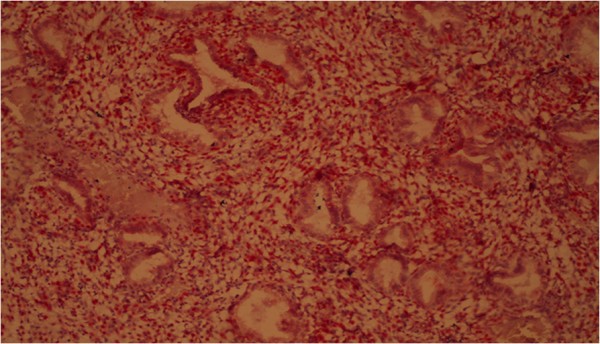

Histologically, we determined in atypical endometrial hyperplasia the glands with numerous ramifications and papillary projections that protruded into the lumen of glands; they are strongly sinuous, with irregular shape. Here and there, glands are closely located to each other without stromal layers and are separated by a narrow strip of connective tissue only. The epithelial cells of glands acquired the features of tumor processes: reduction of nuclear/cytoplasmic ratio, hyperchromatosis, nuclear polymorphism, etc. There were proliferation and increased mitotic activity and abnormal mitosis. Atypical endometrial hyperplasia is shown in Figure 12.

Figure 12

Atypical glandular hyperplasia of the endometrium. Coloring by hematoxylin-eosin (×40).